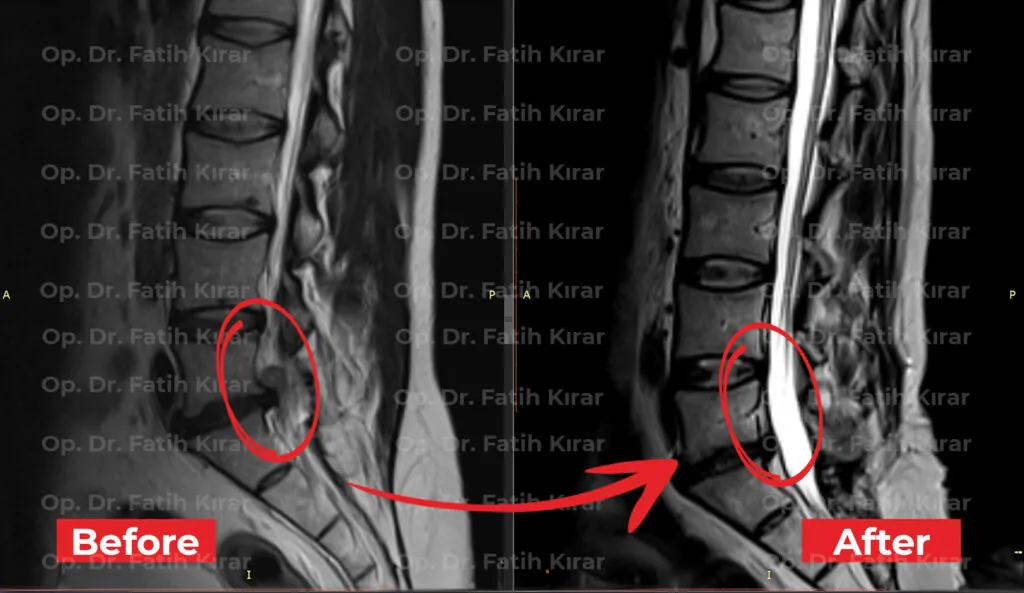

MR Images

Pre and post-treatment MR images of our patients

Former star player of Real Madrid and Spanish National Team Fernando Morientes came to Turkey for back hernia treatment. He regained his health with applied regression and robotic laser treatments.